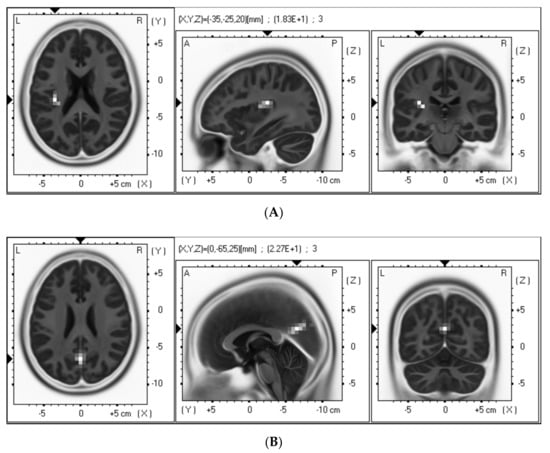

| Type of Massage | Brain Region | BA | MNI Coordinates | p-Value |

|---|---|---|---|---|

| (x, y, z) | ||||

| Hand | Insular cortex | 13 | 35, 0, 15 | <0.05 |

| Foot | Left posterior cingulate cortex | 31 | 10, −70, 15 | <0.05 |

| Right posterior cingulate cortex | 31 | −10, −75, 20 | <0.05 |